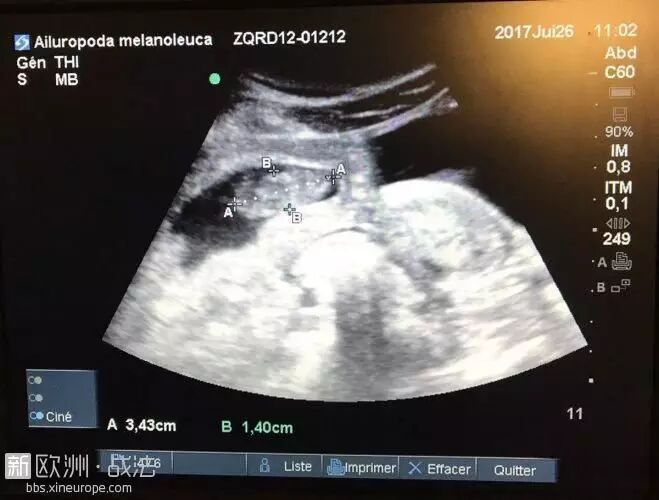

“欢迎熊猫宝宝!法国动物园的熊猫首次怀孕了”,据法新社26日报道,法国博瓦勒动物园当日透露,2012年赴法的雌性大熊猫“欢欢”怀孕了!

法新社称,让大熊猫怀孕是众所周知的困难,雌性熊猫每年仅发情不超过48小时。去年,“欢欢”曾有过一次“假怀孕”。动物园方面表示,“欢欢”并非自然受孕,而是由动物园做的人工授精。

动物园预测,此熊猫宝宝将于8月4日或5日降生。